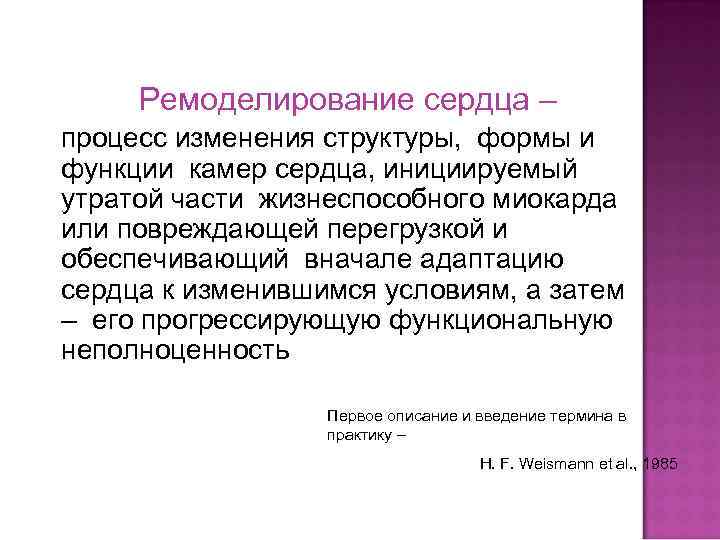

Ремоделирование сердца – процесс изменения структуры, формы и функции камер сердца, инициируемый утратой части жизнеспособного миокарда или повреждающей перегрузкой и обеспечивающий вначале адаптацию сердца к изменившимся условиям, а затем – его прогрессирующую функциональную неполноценность Первое описание и введение термина в практику – H. F. Weismann et al. , 1985

Ремоделирование сердца – процесс изменения структуры, формы и функции камер сердца, инициируемый утратой части жизнеспособного миокарда или повреждающей перегрузкой и обеспечивающий вначале адаптацию сердца к изменившимся условиям, а затем – его прогрессирующую функциональную неполноценность Первое описание и введение термина в практику – H. F. Weismann et al. , 1985